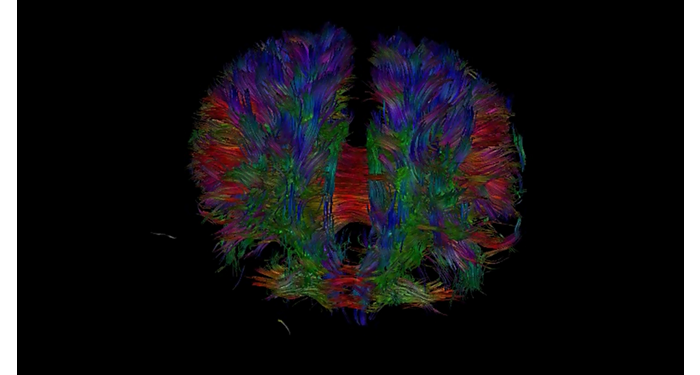

70% of radiologists consider neuro indications to be challenging, mostly due to a lack of appropriate imaging and visualization techniques¹. Philips aims to provide the best possible diagnostic clarity and treatment guidance for all patients with neurological disorders. By leveraging our dStream digital platform, this year, we are introducing, a set of novel imaging and visualization strategies. These may empower you to resolve complex neuro questions with more certainty, as well as unlock new neuro territories in advanced Neurofunctional applications. This is a key step towards elevating neuro diagnostics and ultimately touching more lives with MR imaging. ¹ TMTG Market Survey 2016

New neuro applications